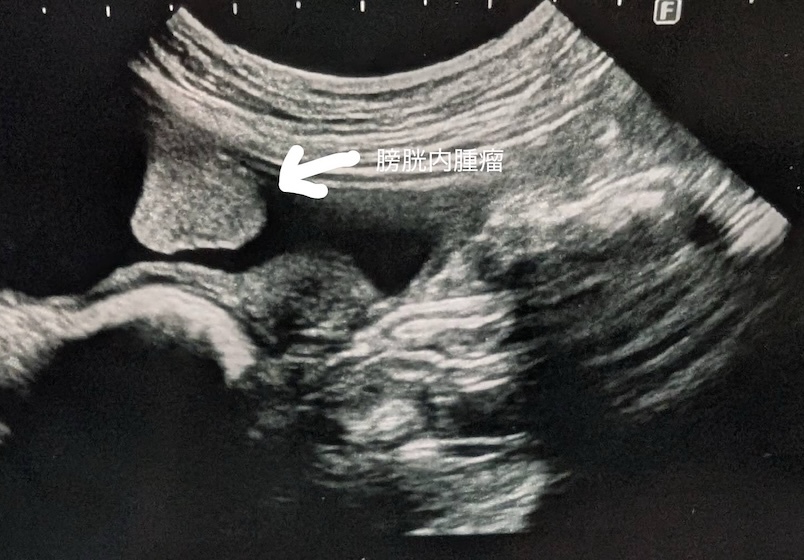

膀胱腫瘤(2025/11/25)

犬猫共に、膀胱内に腫瘤が発生することがあり、その場合には排尿しづらそうな様子や、血尿、頻尿といった、膀胱炎などと同様の症状がよく認められます。超音波検査を行うことで、膀胱内に腫瘤が形成されているかどうかを確認することが出来ます。また、カテーテルを用いて採材を行い、細胞診検査や遺伝子検査を行うことで診断を行います。診断後、腫瘤の発生状況などにより、外科的/内科的治療を検討していきます。膀胱内腫瘤を認めた場合には悪性腫瘍であることが比較的多いこともあり、普段と異なる排尿の様子が認められた場合などは、お早めにご相談下さい。

獣医師 池田